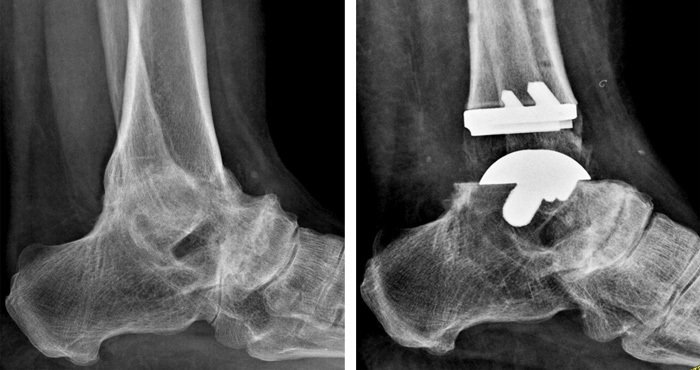

Radiografia in movimento

La radiografia in movimento mostra lo spazio articolare ripristinato e la distanza tra tibia e astragalo. Il movimento risulta fluido e scorrevole, simile a quello fisiologico. Il risultato che si deve ottenere al termine dell’intervento di Protesi di Caviglia è la normale mobilità della caviglia in flesso-estensione.